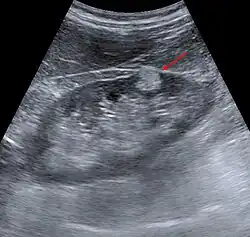

Angiomyolipom der Niere in der Sonographie. Der Tumor ist echoreich (hell).

• Im Ultraschall finden sich durch den Fettgehalt stark echogene Raumforderungen in der Niere.